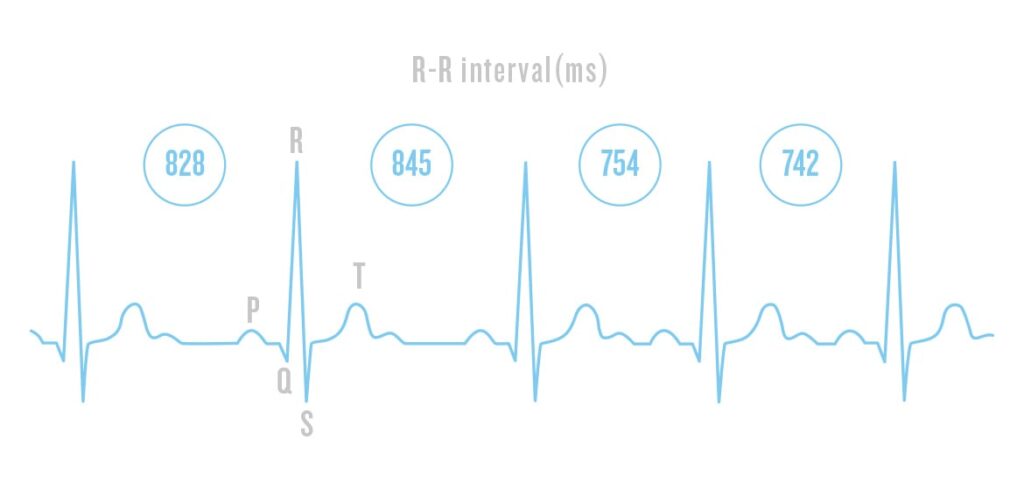

HRV refers to the variation in time between your heartbeats. It’s measured in milliseconds and represents how adaptable your autonomic nervous system (ANS) is. A higher HRV typically means your body is well-rested and resilient to stress, while a lower HRV can indicate fatigue, overtraining, or insufficient recovery.

- High HRV: Good recovery, strong parasympathetic response

- Low HRV: Fatigue, stress, sympathetic dominance